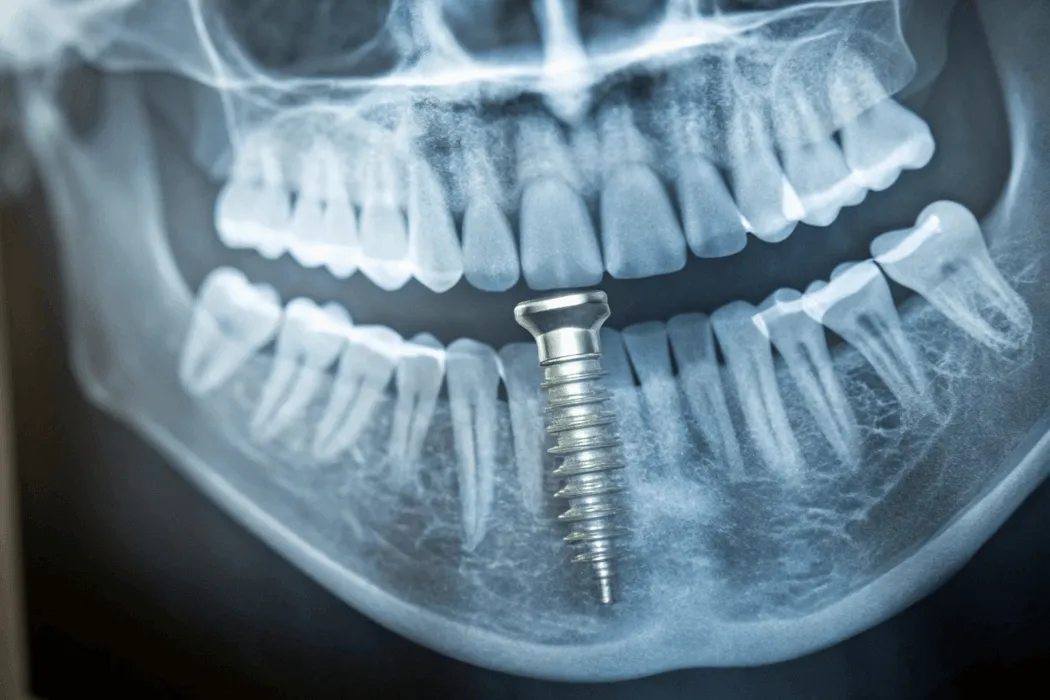

Po umieszczeniu implantu w kości rozpoczyna się tzw. osteointegracja, czyli proces zrastania się implantu z tkanką kostną. To kluczowy moment, który decyduje o trwałości i stabilności całego leczenia.Wyróżnia się kilka głównych faz gojenia:

• Osteointegracja (3–6 miesięcy) – w tym czasie implant zrasta się z kością. To najważniejsza faza, która warunkuje późniejszą trwałość korony lub mostu.

• Ostateczna odbudowa protetyczna – po zakończeniu integracji zakładana jest korona, most lub inny rodzaj uzupełnienia.